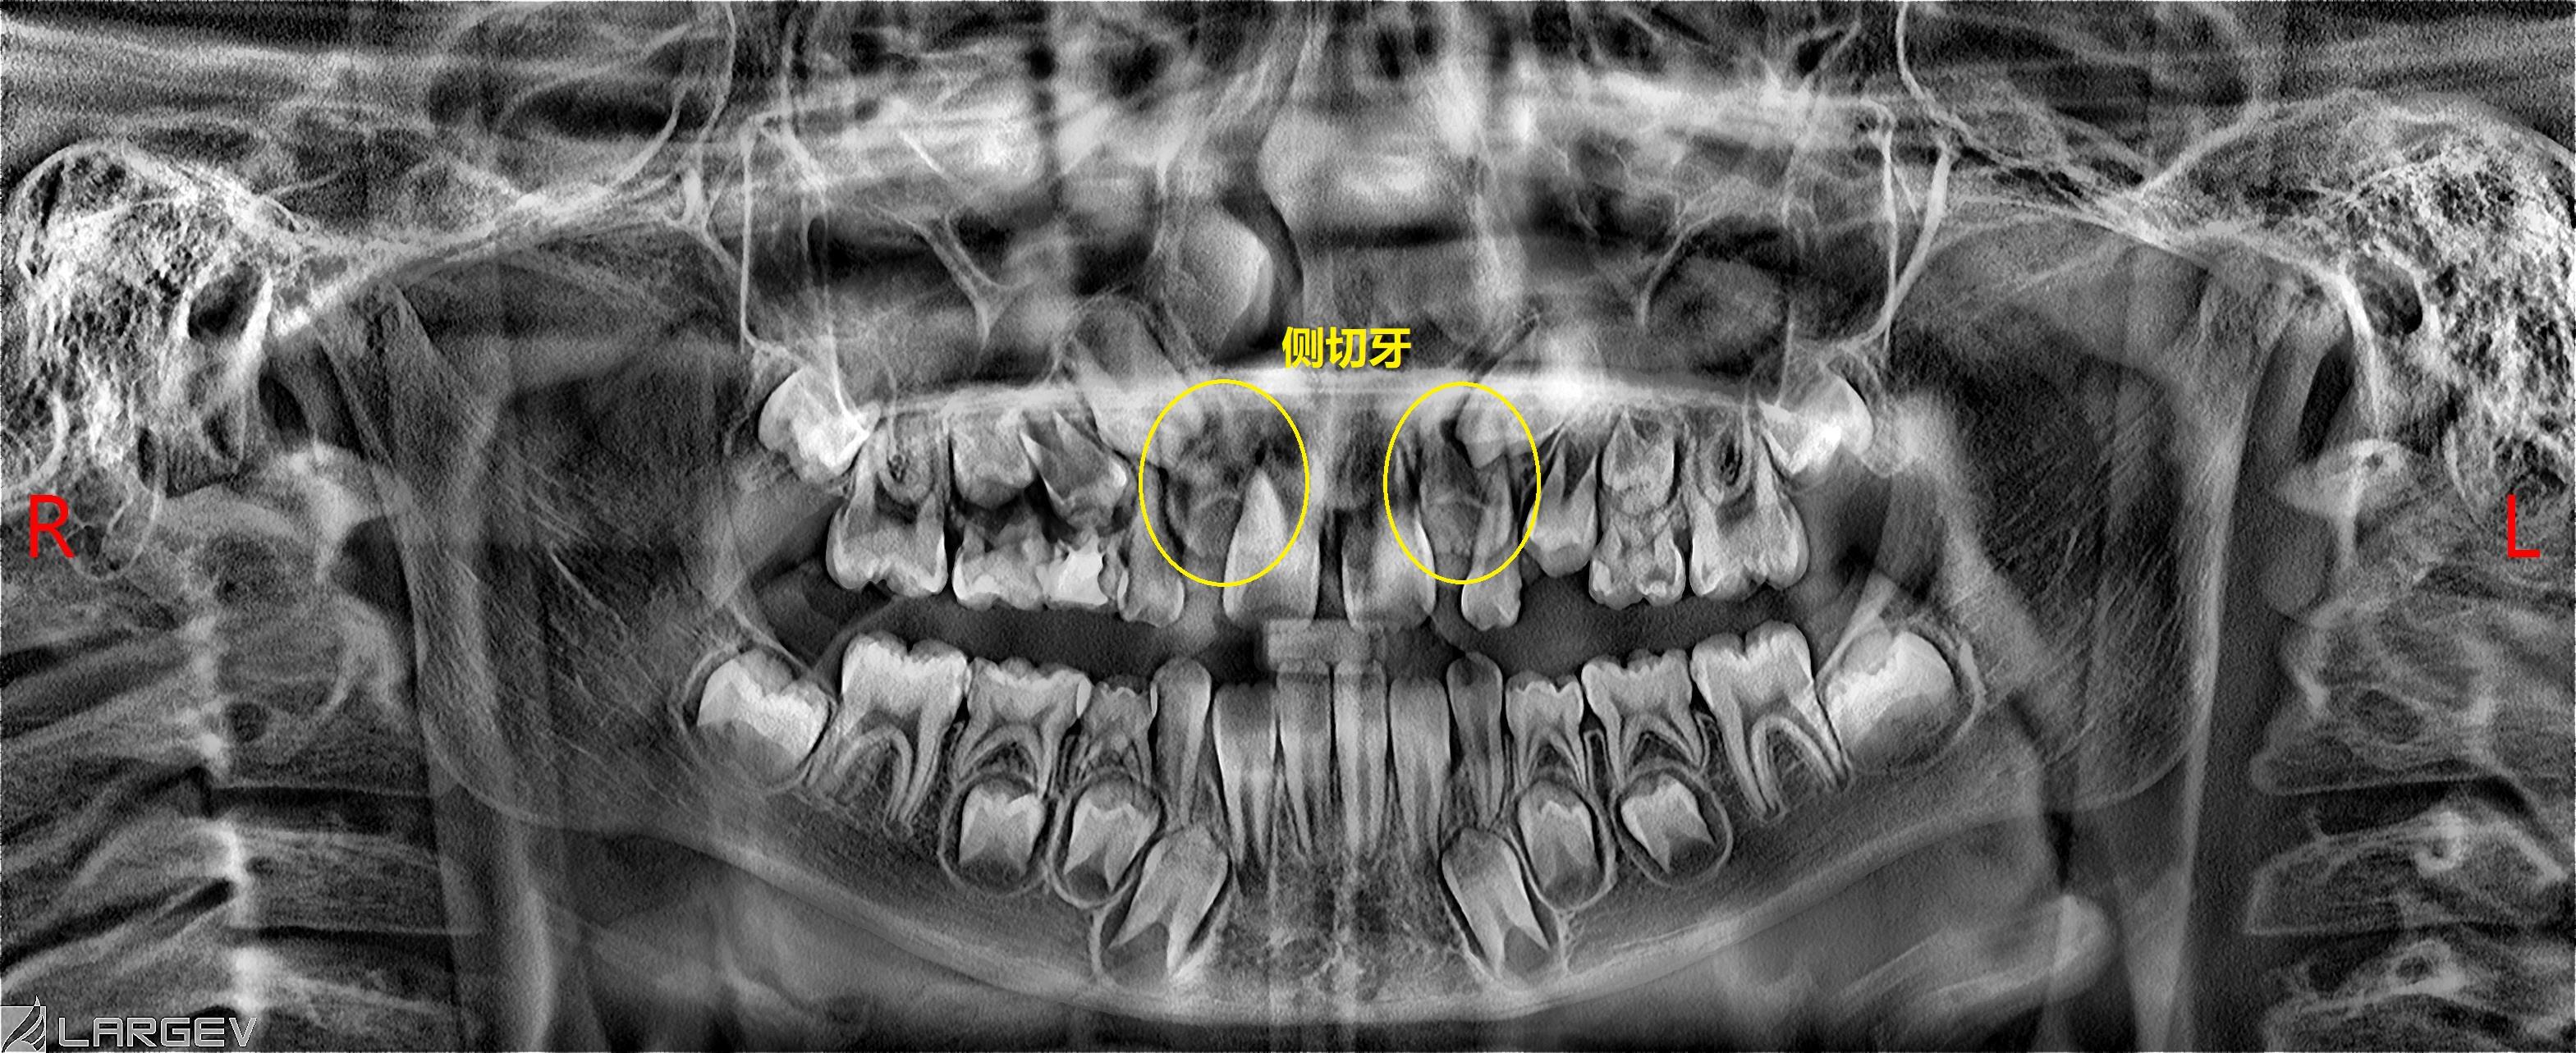

原因一:侧切牙牙胚的挤压

中切牙刚刚萌出,侧切牙的牙胚在牙槽骨内,挤压在中切牙牙根旁,这样就导致中切牙萌出的牙冠向远中倾斜,并且两颗牙中间有个缝。这种情况家长们不用焦急,它们会随着侧切牙的萌出有所改善。